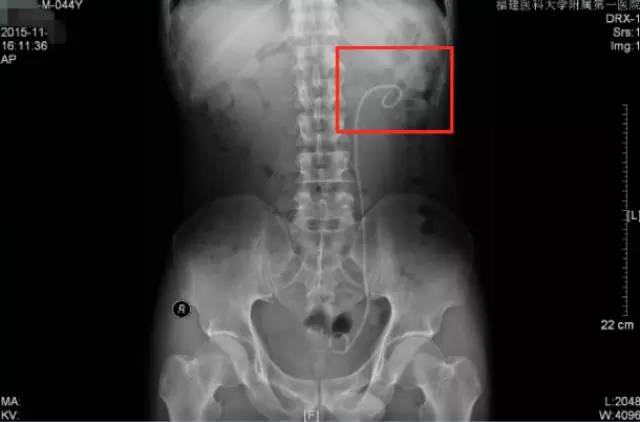

手术前KUB

术后复查KUB

通过本次术前术后的KUB对比,可以看到,经过这次手术,柯先生左肾的大部分结石已经消失了,仅剩下盏的一些小的结石。